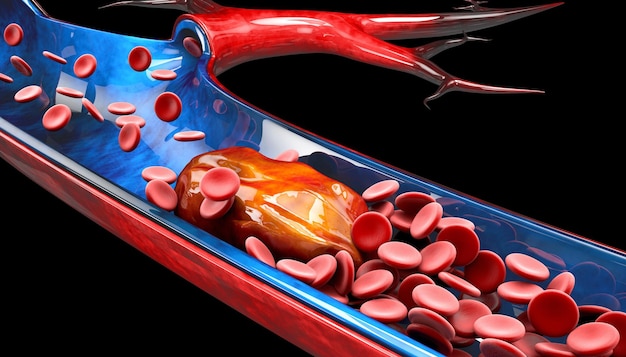

血栓症 イラスト (337 無料写真)

血栓症」のイラスト素材・ベクター画像 - イメージマートimagemart。

人間の血管の医療静脈血栓の図イラスト画像とPSDフリー素材透過の無料ダウンロード - Pngtree。

血栓塞栓症」の1063点のロイヤリティフリー画像、写真素材、絵Shutterstock。

5,800点を超える血栓のイラスト素材、ロイヤリティフリーのベクター素材グラフィックスとクリップアート - iStock血管, 血小板, 心臓。

5,800点を超える血栓のイラスト素材、ロイヤリティフリーのベクター素材グラフィックスとクリップアート - iStock血管, 血小板, 心臓。

5,800点を超える血栓のイラスト素材、ロイヤリティフリーのベクター素材グラフィックスとクリップアート - iStock血管, 血小板, 心臓。

正常な血管と血栓ができた血管 イラスト素材5358451- フォトライブラリ。

5,800点を超える血栓のイラスト素材、ロイヤリティフリーのベクター素材グラフィックスとクリップアート - iStock血管, 血小板, 心臓。

血栓ができている血管 イラスト素材6665451- フォトライブラリ。

5,800点を超える血栓のイラスト素材、ロイヤリティフリーのベクター素材グラフィックスとクリップアート - iStock血管, 血小板, 心臓。